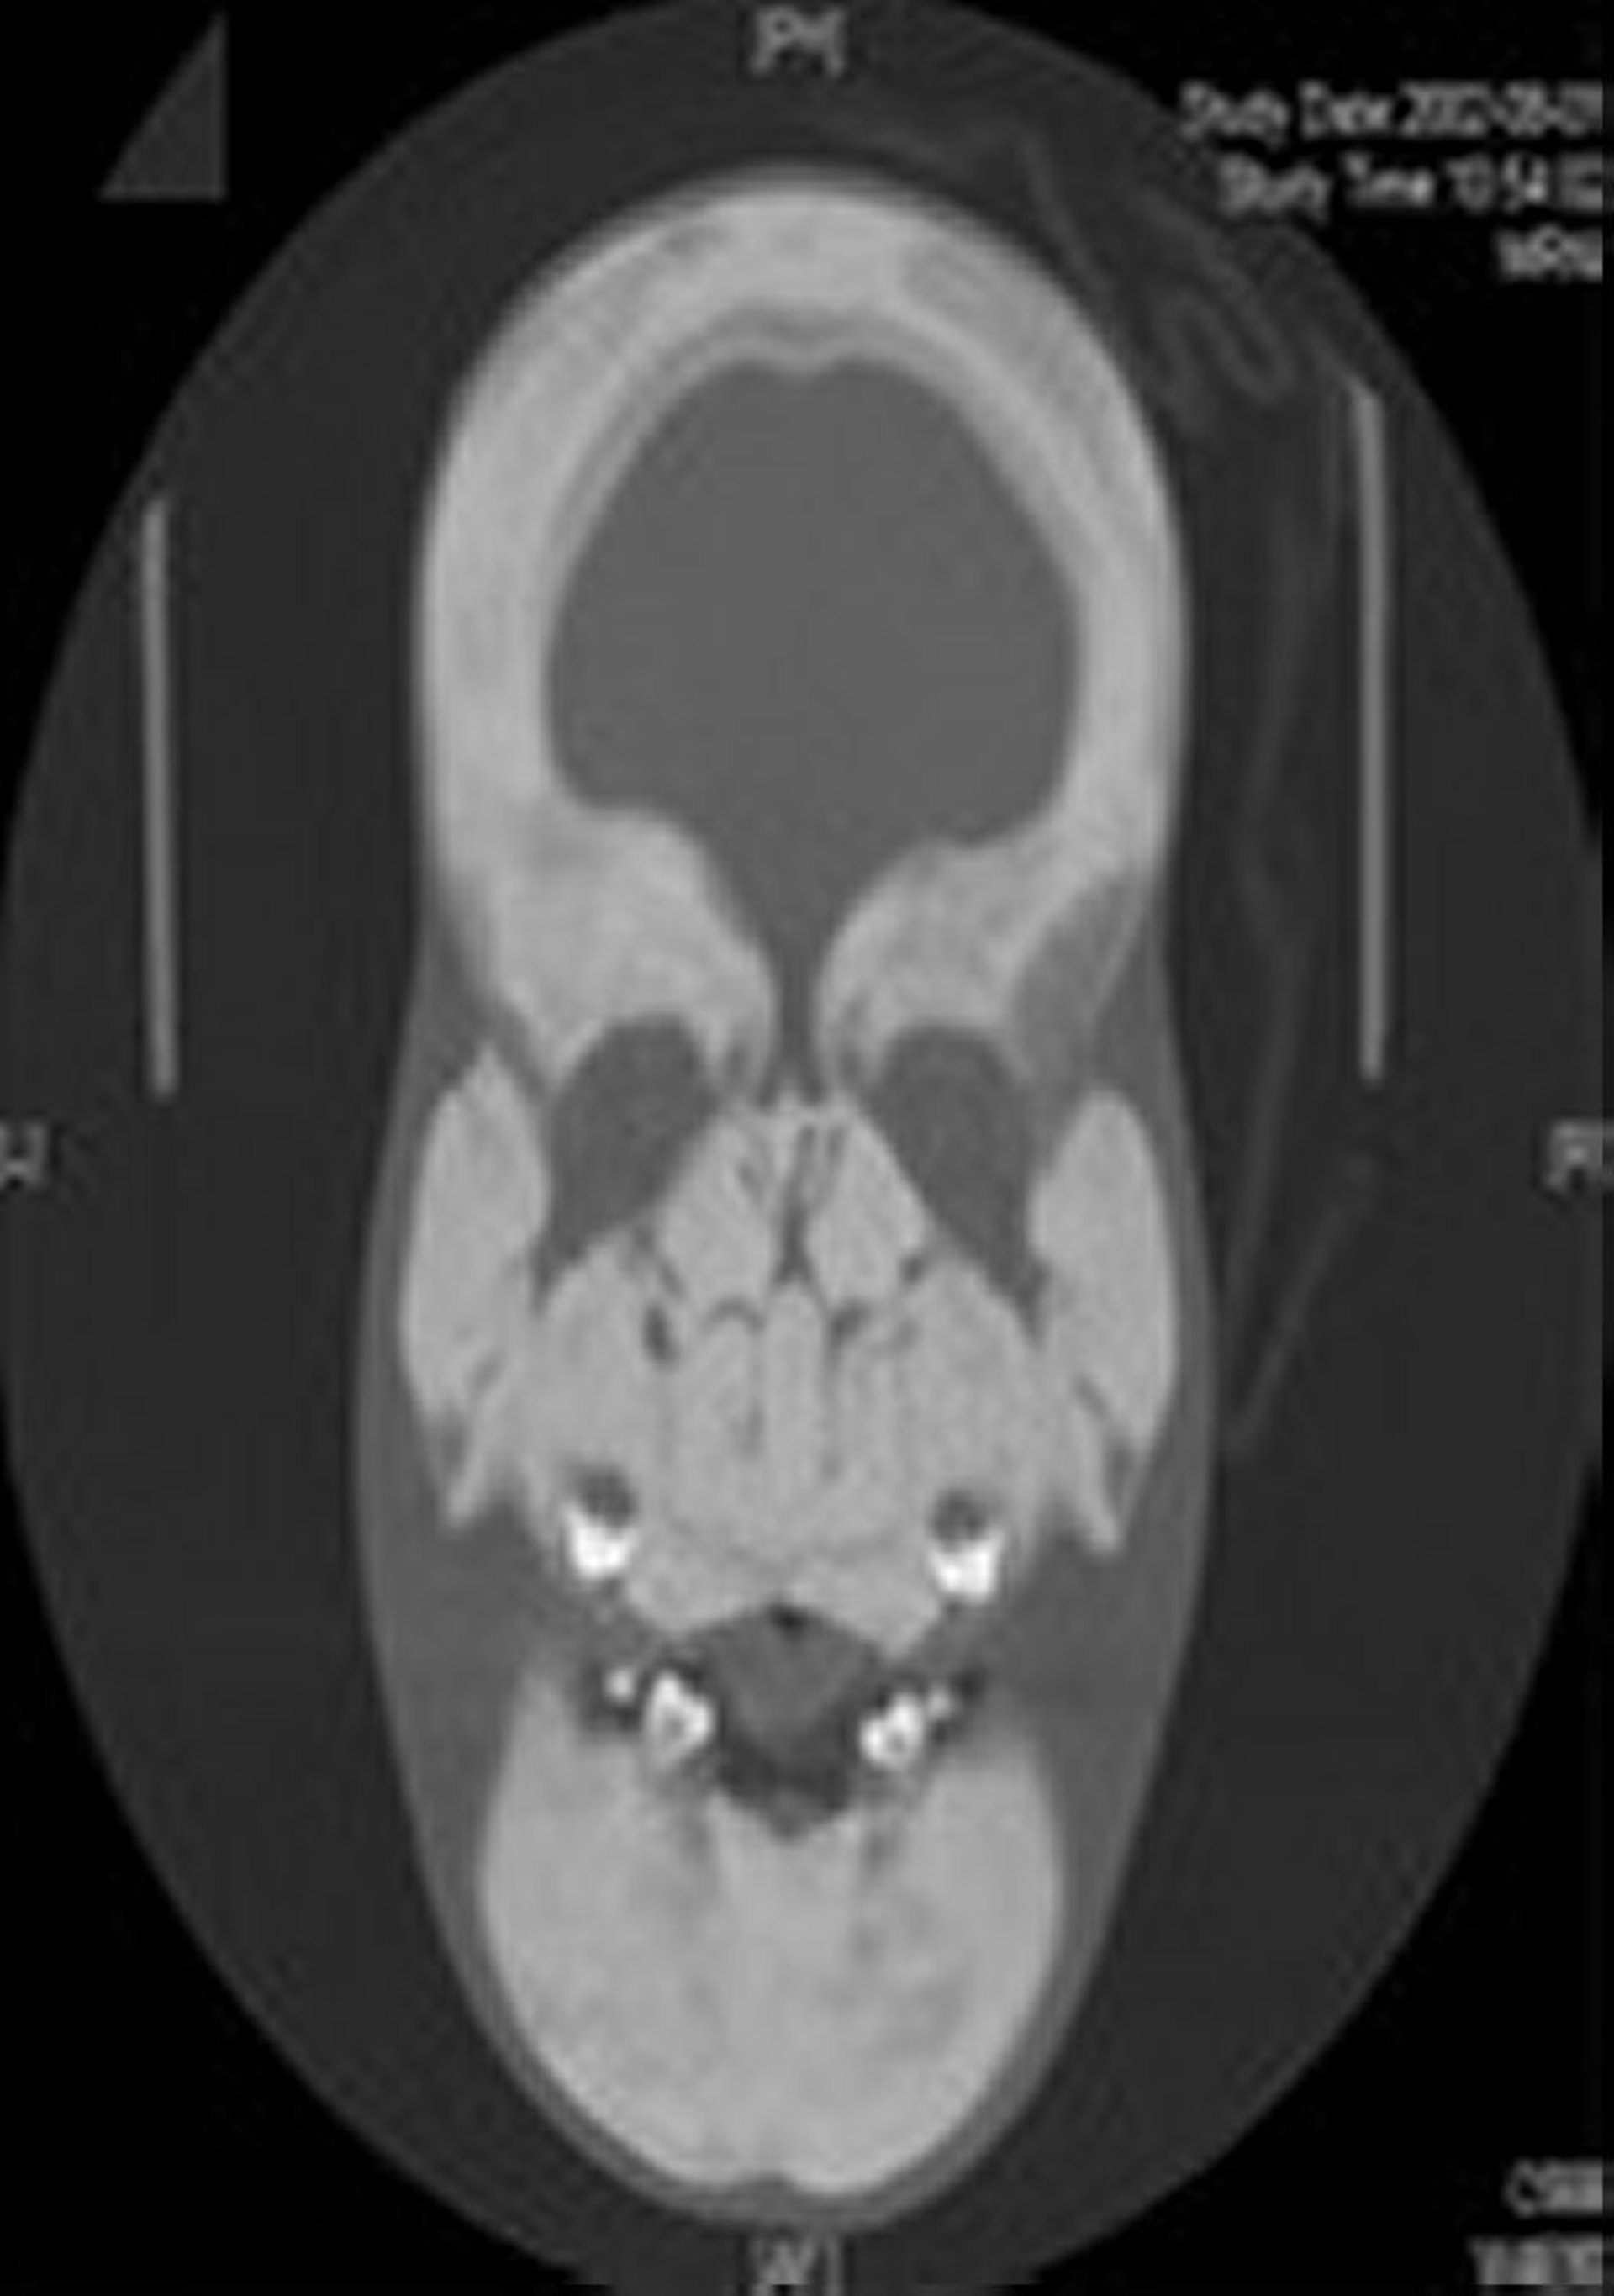

La diagnosi di sclerosteosi viene sospettata da anomalie scheletriche caratteristiche, in particolare quando il paziente presenta anche sindattilia. In genere, vengono eseguite radiografie standard (dirette). Le principali manifestazioni radiografiche del cranio sono l'ingrossamento e la sclerosi della volta cranica e della mandibola. I corpi vertebrali sono risparmiati, sebbene i loro peduncoli presentino una maggiore densità. Le ossa della pelvi sono sclerotiche, ma hanno contorni normali. Le ossa lunghe sono sclerotiche, le corticali sono iperostosiche e le diafisi si presentano iposviluppate. È disponibile un test genetico diagnostico.

Questa radiografia mostra un marcato ispessimento e sclerosi del cranio e delle ossa facciali intere.